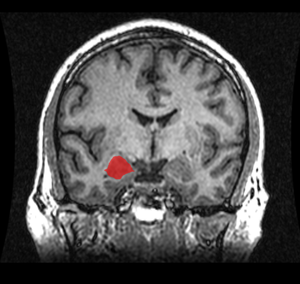

لوزة المخ amygdalaecorpus amygdaloideum؛ باللاتينية، من اللاتينية ἀμυγδαλή, amygdalē، 'almond', 'tonsil'[1])، مدرجة في تشريح گراي باسم nucleus amygdalæ، هي مجموعتين من النوى على شكل لوزة تقعان في المنطقة العميقة والوسطى داخل الفص الصدغي في المخ لدى الثدييات المتطورة، ومنها البشر.[2] أظهرت الأبحاث أن للوزة المخ دوراً أساسياً في معالجة الذاكرة، صنع القرار، وردود الفعل العاطفية، وتعتبر لوزة المخ جزءاً من الجهاز الحوفي.[3]

تشكل لوزة المخ جزءاً من الجهاز الحوفي، وتشارك في إدراك وتقييم العواطف والمدارك الحسية والاستجابات السلوكية المرتبطة بالخوف والقلق وهي تراقب باستمرار ورود أي إشارات خطر من حواس الإنسان تعتبر كنظام إنذار واستشعار للمتعة.